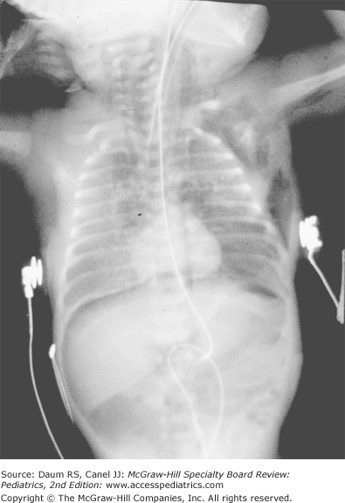

The patient's abdominal radiograph improves during the next few days. The platelet count is stable.

Which is the most likely complication of necrotizing enterocolitis (NEC)?

The correct answer is A. Strictures happen in about 10% of patients following NEC. Sepsis at this point is related to physician interventions such as indwelling vascular catheters placed for prolonged hyperalimentation.